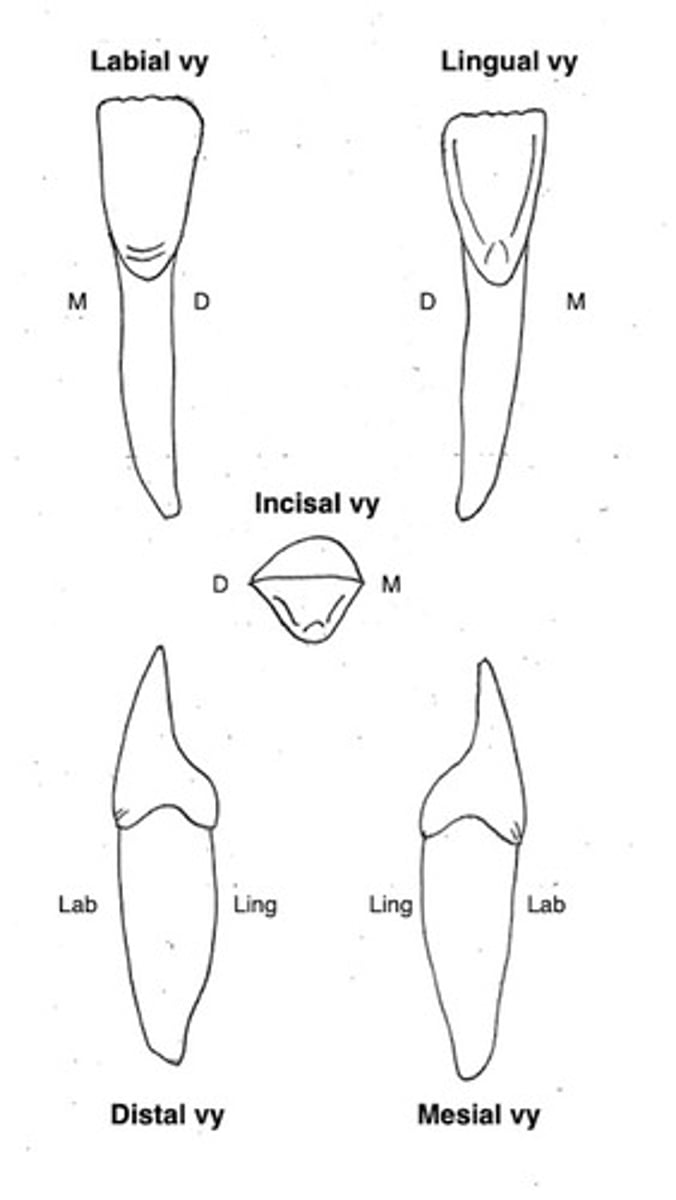

Underkäkens canin (33 och 43)

Kronans form?

Storlek?

Övrigt?

Kronans form

1 kusp, skänklarna är olika långa (mesiala kortare)

smal i mesiodistal riktning

plan mesialt

tydligt böjningstecken

saknar oftast cingulum

tydlig kronflykt

Storlek

bettets längsta krona, lång och smal rot

Övrigt

väldigt plan hela vägen och en bit ner på roten